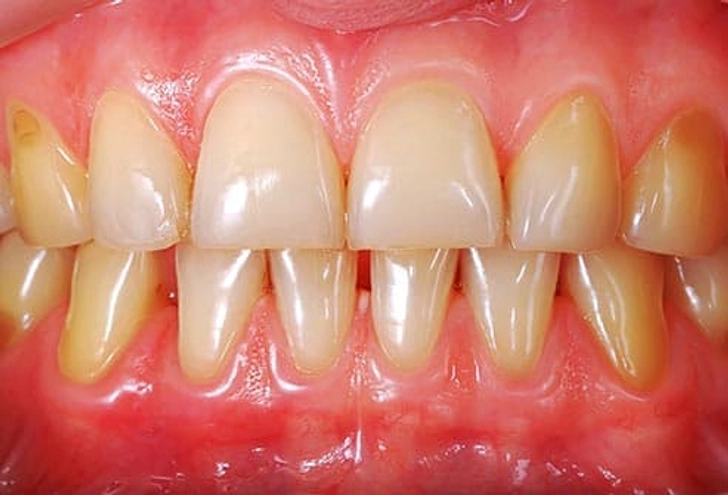

۱۱. مشکلات لثه

اگر لثههایتان به راحتی خونریزی میکنند، حساس هستند یا عقبنشینی کردهاند، احتمال بیماری لثه (Gingivitis) وجود دارد. پلاک زیر خط لثه عامل اصلی است. اگر درمان نشود میتواند منجر به از دست رفتن استخوان، لق شدن دندانها و مشکلات گفتاری یا جویدن شود. پیشگیری شامل مسواک، نخ دندان، دهانشویه آنتیسپتیک و جرمگیری منظم است.